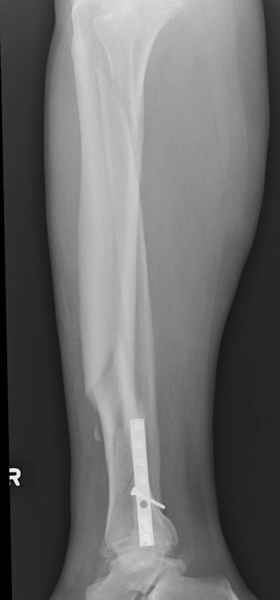

Повреждение такой локализации, на которой применимы и аппарат (классический Илизарова или гибридный), пластина, особенно Locked Plate, и гвоздь с блокированием. В нашей клинике был бы выполнен закрытый интрамедуллярный остеосинтез. Желательно использовать гвоздь с возможностью провести более чем 2 обычных фронтальных винта в дистальном отломке.

Здесь мы использовали новый Synthes Nail с дополнительными дырками, в проксимальной части 4: по две косых и поперечные (один стандартный а другой динамический), в дистальной части две поперечные, прямая и косая. Вес больного более 120 кг, нагрузку начнем через месяц.